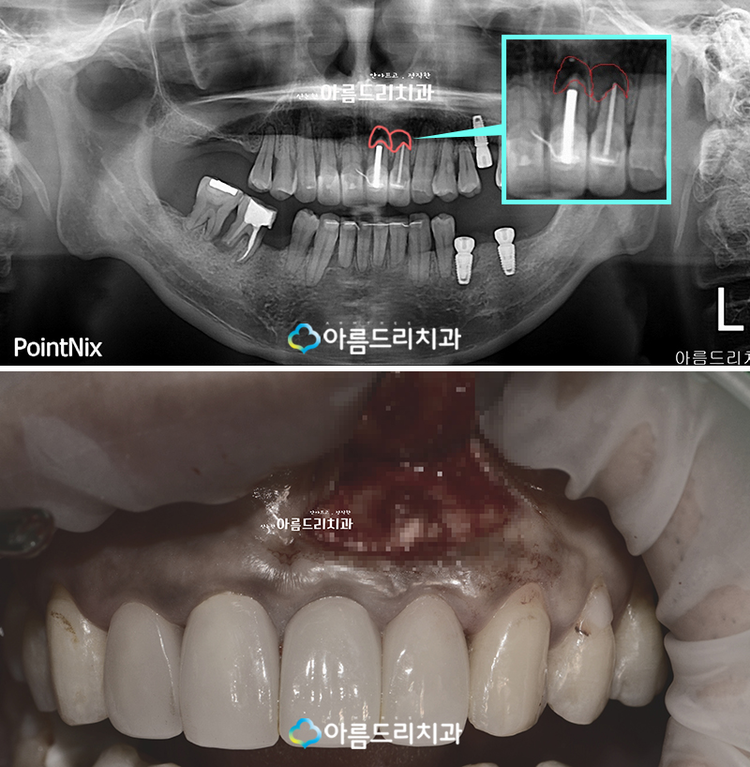

우선 환자분의 치아에 대한 파노라마

X-ray 촬영을 해본 결과 전치부쪽 예전에

신경치료를 했던 부위의 뿌리쪽 염증이

발생한 것으로 파악이 되었습니다. 확대한

사진에서 보실 수 있듯이 정상적인 잇몸의

경우 X-ray 상에서 하얗게 나오지만 환자

분의 경우 검은 부분을 확인해 보실 수

있으실 겁니다. 다시 재신경치료를 하게

되더라도 뿌리쪽의 염증은 제거할 수 없는

경우가 많기 때문에 치근단절제술 후기를

통하여 다시 치아를 살리는 치료를 해야할

것으로 아름드리 의료진은 판단하였습니다.